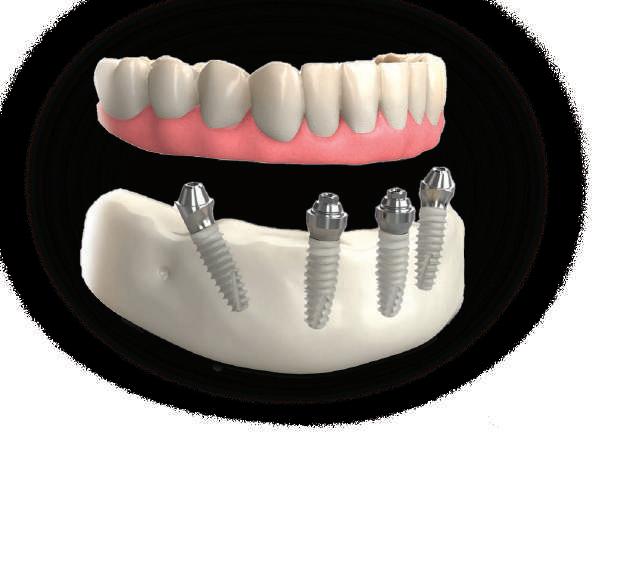

Dental Tribune Bulgarian Edition / октомври 2022 г.16 клиничен случай с алайнери Г орният латерален ре зец е вторият найчесто вродено липсващ зъб.1,2 Поради разполо жението му във видимата зона на усмивката лечение то на подобни случаи нала га мултидисциплинарен под ход, целящ отличен функцио нален и естетичен резултат. Налице са няколко лечебни мо далности, свързани с различ но разпределение на място то: първият вариант е орто донтско отваряне на място и възстановяване на липсва щия зъб с конструкция, под държана от съседните зъби3 или от имплант4, докато при втория подход разстоянията се затварят и премоларът заема мястото на канина.5 Изборът на лечебен подход трябва да бъде направен съв местно от зъболекар и паци ент въз основа на очакванията на последния и предвиди мостта на лечението. Множе ство фактори влияят върху това решение, като напри мер типа малоклузия, размера, формата и цвета на кучеш ките зъби6, оклузалните вза имоотношения (овърджет и овърбайт), лицевия профил, дължината на зъбната дъга и несъответствията в разме ра на зъбите.7 В настоящата публикация се разглежда случаят на жена в зряла възраст с вродена лип са на горен ляв латерален резец. Бяха приложени про зрачни алайнери за отваряне на място за единичен им плант и бяха постигна ти функционална оклузия и отлична естетика. ПРЕДСТАВЯНЕ НА СЛУЧАЯ Диагноза Пациентката бе на 32 годи ни, когато лечението започна, и първоначалното ѝ състоя ние бе следното (фиг. 1–3): липсващ горен ляв латерален резец; клас II, подклас I малоклузия; отклонение на горната сре динна линия вляво; Доклад на клиничен случай ЛЕЧЕНИЕ С АЛАЙНЕРИ НА ПАЦИЕНТ С АГЕНЕЗИЯ НА ЛАТЕРАЛЕН РЕЗЕЦ Д-р Iro Eleftheriadi и д-р Christodoulos Laspos, Гърция и Кипър Фиг. 1a–h Предоперативни лицеви и интраорални снимки. Фиг. 2a–e Дигитални модели преди началото на лечението. Фиг. 3 Панорамна снимка преди лечението. Фиг. 1a Фиг. 1d Фиг. 1f Фиг. 2a Фиг. 2d Фиг. 2b Фиг. 2e Фиг. 3 Фиг. 2c Фиг. 1b Фиг. 1e Фиг. 1g Фиг. 1h Фиг. 1c

Цели на лечението и лечебен план Целите на лечението бяха следните: нивелиране и подреждане на зъбите и в двете зъбни дъги; отваряне на пространство за липсващия латерален резец; коригиране на отношенията при канините и моларите до клас I; и корекция на отклонението на срединната линия. Лечебният план включваше: корекция на отношенията при кучешките зъби и мола рите до клас I с дистализира не на максилата; отваряне на пространство в областта на #22 за поставя не на единичен имплант; корекция на срединната ли ния; и създаване на място за раз ширяване на зъб #12 и апрок симална редукция в долната челюст с цел подобряване на несъответствието по Болтън и осигуряване на подобра оклузия. Изпълнение на лечебния план Този случай бе изпълнен със системата за алайнери Invisalign (Align Technology). Одобреният първоначален лечебен план предвиждаше 49 алайне ра с дистализиране на задни те горни зъби до клас I (прибли зително с около 3.5 мм; фиг. 5). За бъдещия имплант в областта на липсващия латерал бе планирано пространство от 6.5 мм, докато във фронталния сегмент на долната челюст бе предвидена апроксимална редук ция. В дясната страна бутон за ластици клас II бе поставен на зъб #47 вместо на зъб #46, за да не се увреди короната на импланта. Понеже пациентката жи вееше в чужбина,

планта бе поставена временна коронка (фиг. 10 и 11), докато бъде изготвена окончателна та. Бе постигнат отличен кра ен резултат. Меките тъка ни около импланта напълно заздравяха, което доприне се за перфектната хармония между бяла и розова естетика (фиг. 12–15).